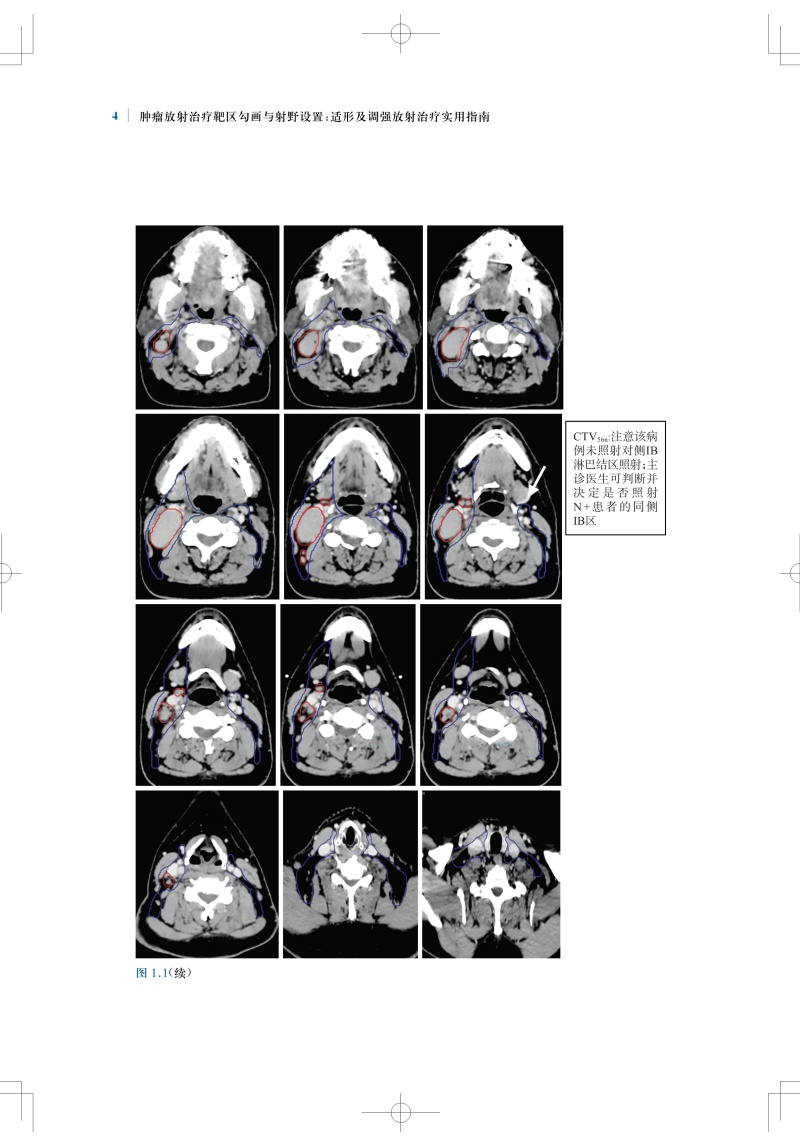

肿瘤放射治疗靶区勾画与射野设置是疗效的基石,精准的靶区范围的确定和勾画可确保肿瘤患者的放疗效果。全书结合大量影像图片,按章分别详细介绍了各种常见病变的具有临床依据的精确的CTV勾画和指南,包括鼻咽癌、甲状腺癌、早期乳腺癌、肺癌、直肠癌、前列腺腺癌、膀胱癌等;并对相关的淋巴引流区解剖进行了勾画,且逐层显示并说明注意事项。本书内容实用,可为放疗医师对常见肿瘤进行适形放疗和调强放疗时的靶区勾画及放射野设置提供指导和参考。